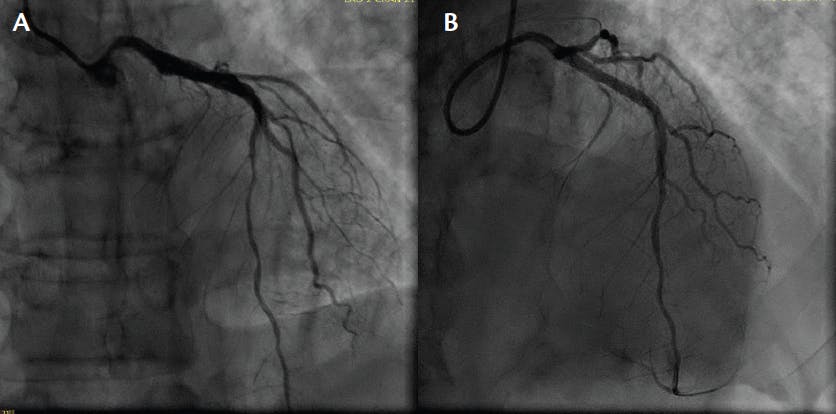

A man in his late 40s with a history of daily cigarette smoking presented to the ED with retrosternal chest pain. ECG was performed and showed evolving anterior ST-segment changes and high-sensitivity troponin at 1300 ng/L, and a bedside echocardiogram showed an LVEF of 30% with anteroseptal wall motion abnormalities. A coronary angiogram showed a 100% proximal LAD occlusion (Figure 1) and primary PCI with a 40- X 28-mm drug-eluting stent achieving good angiographic results (Figure 2). SSO2 protocol was implemented immediately after PCI.

Figure 2. LAO cranial (A) and RAO (B) cranial views after PCI.

RESULTS

The patient was transferred to the cardiac care unit and a follow-up echocardiogram showed an improved LVEF of 40%. Given his low blood pressure, he was started on low doses of guideline-directed medical therapy. The patient has demonstrated 1 year of follow-up in stable cardiac condition with preserved LV function.